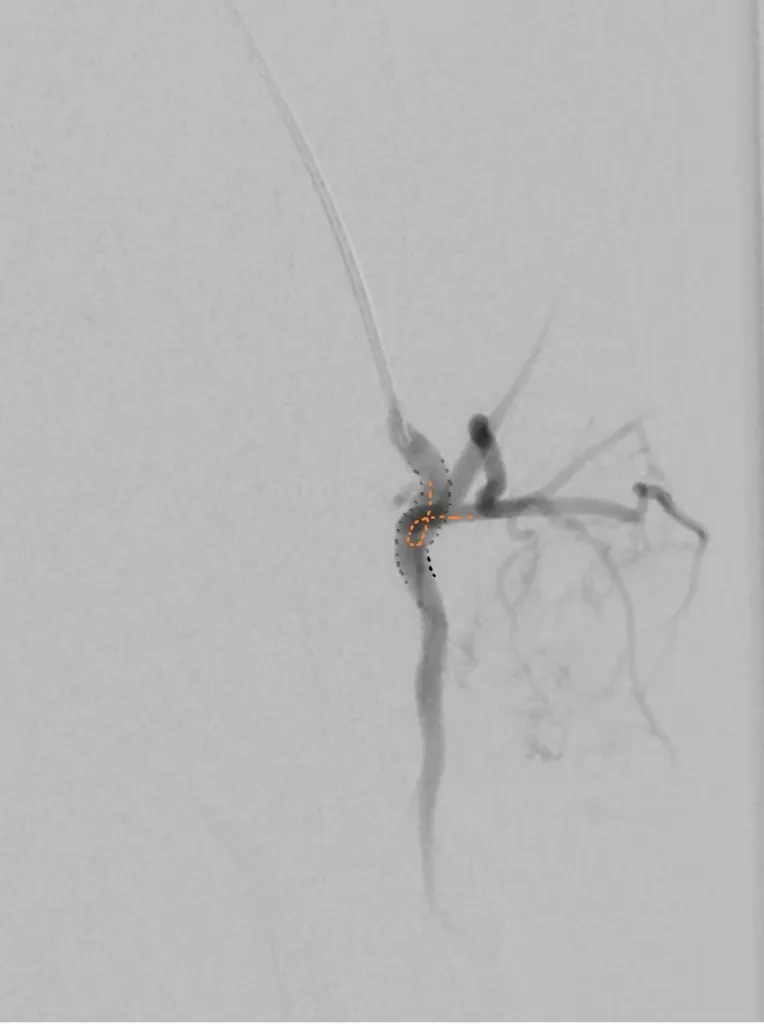

65 year old with a left femoral renal metastasis lesion. Angiograms showing vascularity of the lesion. The two annotated images show the tortuosity of the vessel supplying the lesion. The dotted orange coloured line shows the path of the vessel. It was not possible to cannulate this artery with conventional microcatheters.

Adequate catheter position attained using the Swift Ninja Catheter by Merit Medical. Final image showing reduced vascularity.